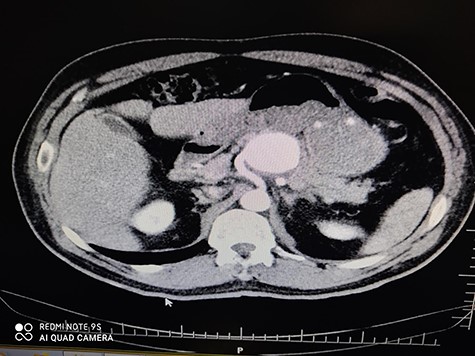

A 56-year-old male (fourth patient) evaluated for abdominal pain was referred to our hospital. In Computed tomography angiography (CTA) giant proximal SAA was diagnosed. We considered endovascular treatment. Angiography was carried out but because of arterial tortuosity wire did not pass through to the distal part of the artery. Hybrid surgery was the next plan. Balloon (7–40) expanded in proximal part of the aneurysm then in laparotomy, distal part was ligated and proximal part according to the inflated balloon was found easily (Fig. 1). After balloon was deflated, aneurysm was ligated and resected (Fig. 2).

Hybrid surgery: Aneurysm sac (Left), Angiography sheath and inflator (Right).